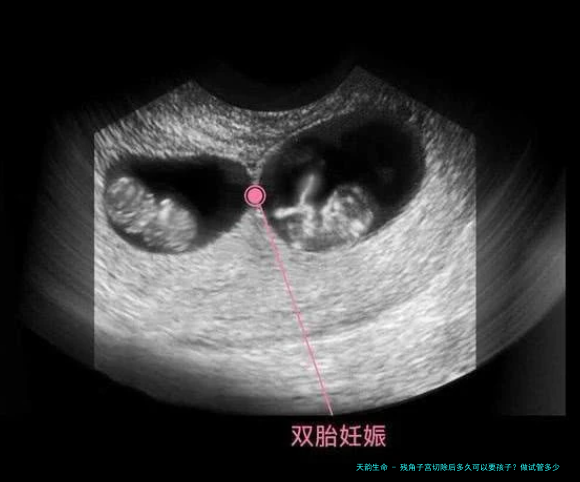

在预备怀孕的过程当中,建议准时进行妇科检查,保障健康状态适宜妊娠。要是存留其他受孕障碍或自然受孕困顿的情况,可以思量通过辅助生育技术(如试管婴儿)完成生育计划。

对于试管婴儿的费用问题,其本钱受许多种要素影响,囊括所处之地区、医院级别、诊疗方案以及个人体质等。大体上,1次完备的试管婴儿周期费用可能在两万至五万元块钱之间。详细费用囊括术前检查、药物促排、卵泡取动手术、胚胎培育及移植等多个环节的花费。